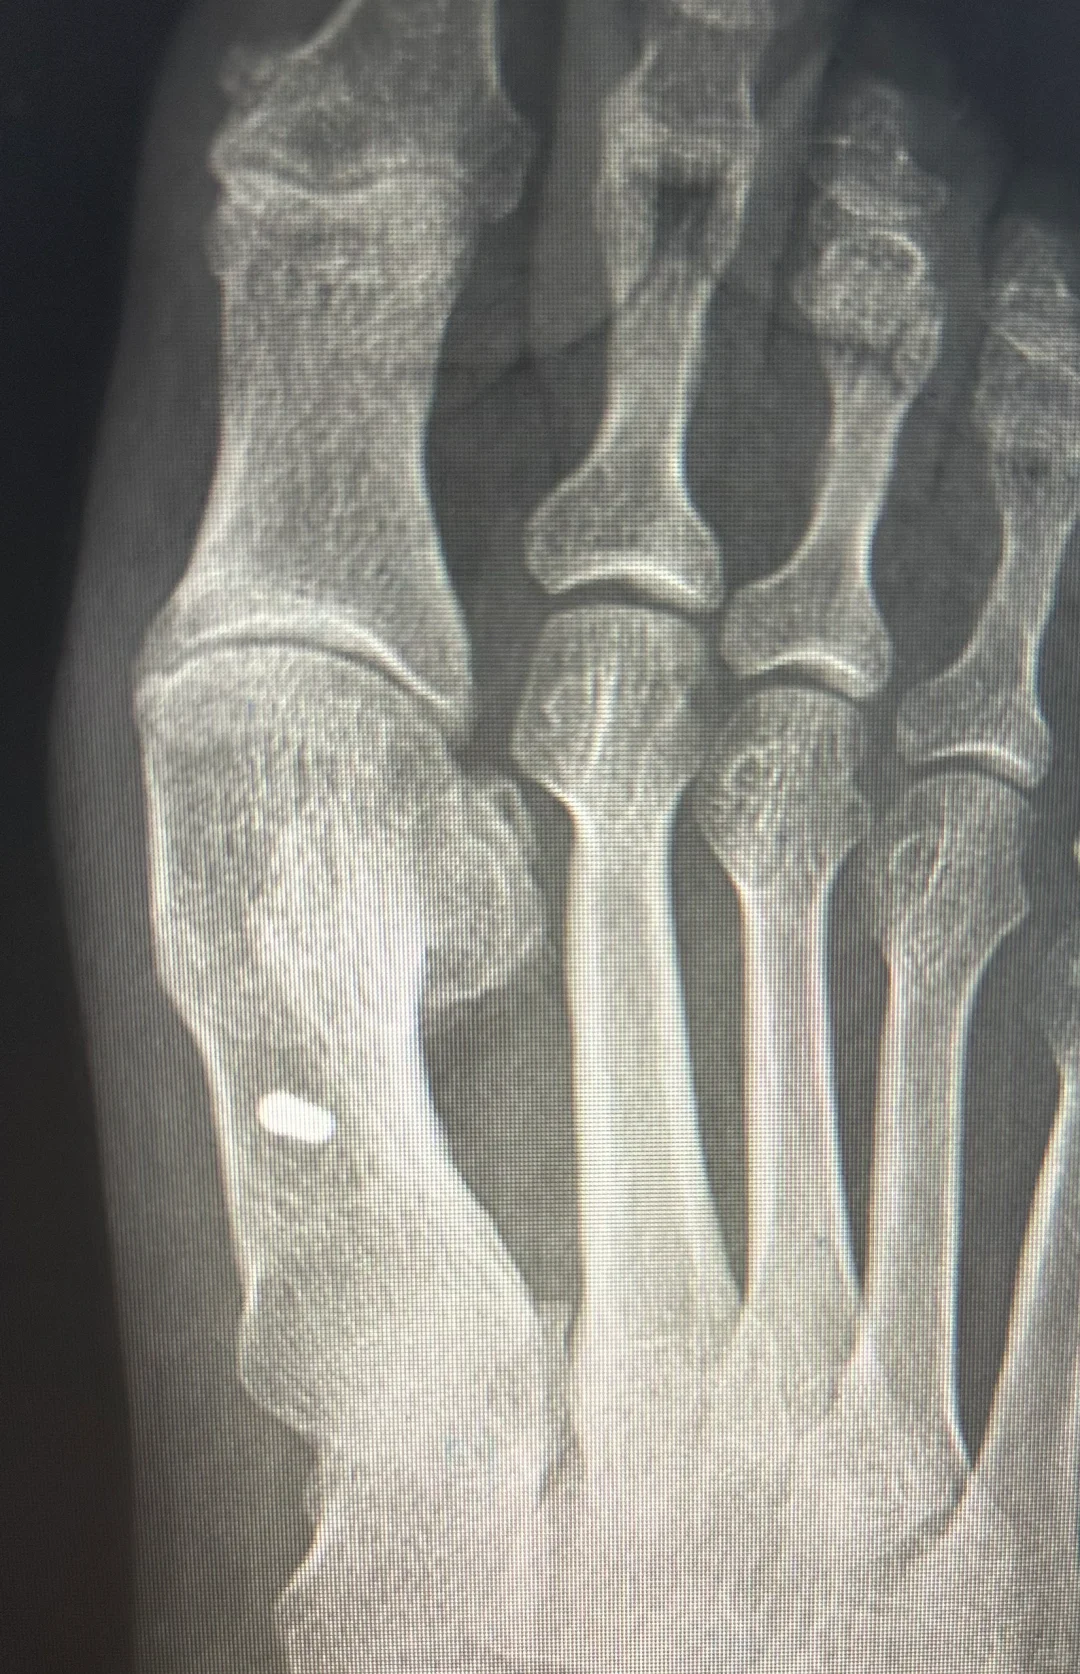

拇外翻术后三年半

手术伤口瘢痕变成白色,术后半年隆起,一年内色深,等2年后慢慢变白。 即使当初缝合愈合并没有那么好,当初没有全部内缝,还有部分外缝的蜈蚣瘢 关节稳定,匹配良好,无不适,没有复发可能 片子上缺损的三角骨区域长满新骨,骨痂下成骨不需要担心。 新骨密度高,都是气质骨,所以强度远高于术前